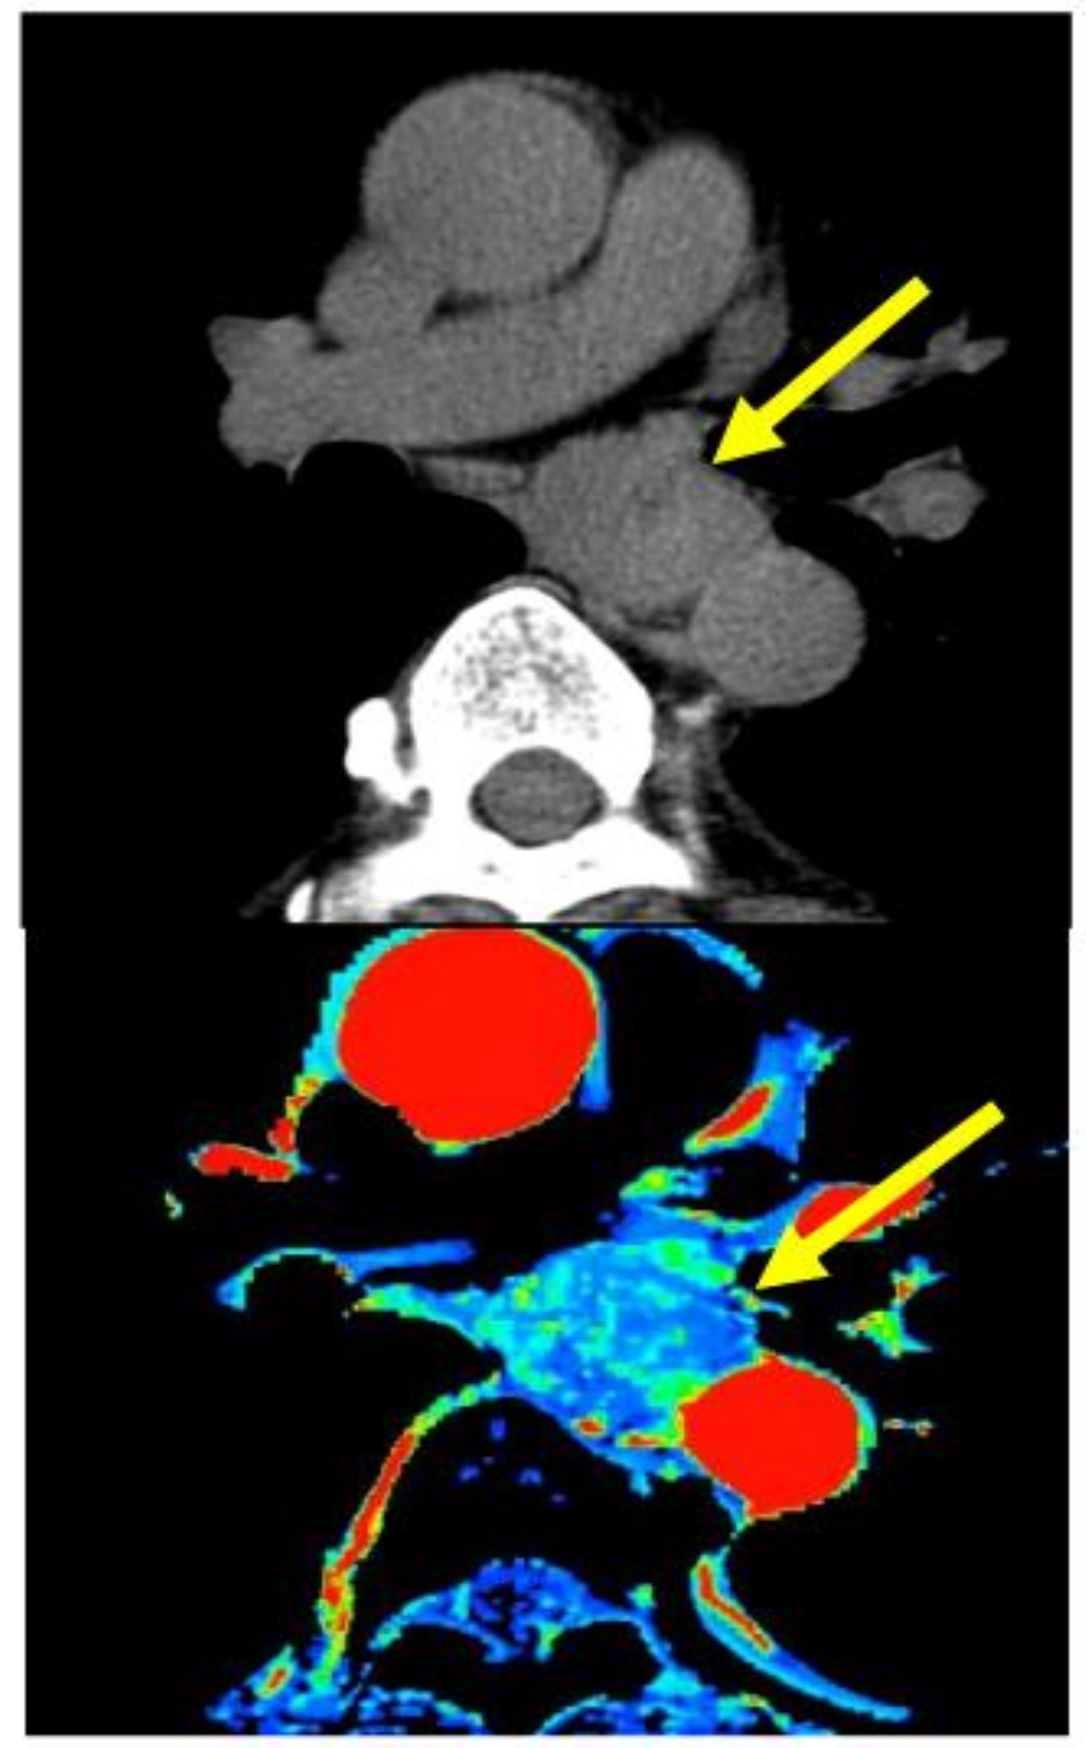

- Hayano, K.; Okazumi, S.; Shuto, K.; Matsubara, H.; Shimada, H.; Nabeya, Y. Perfusion CT can predict the response to chemoradiation therapy and survival in esophageal squamouscell carcinoma: Initial clinical results. Oncol. Rep. 2007, 18, 901–908. [Google Scholar]

- Hayano, K.; Shuto, K.; Satoh, A.; Aoyagi, T.; Narushima, K.; Gunji, H. Tumor blood flow change measured by CT perfusion during chemoradiation therapy (CRT) for monitoring response and predicting survival in patients with esophageal cancer. Esophagus 2014, 11, 72–79. [Google Scholar] [CrossRef]